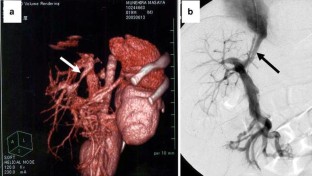

Patent ductus venosus (PDV) is a rare condition, which usually presents secondary to hepatic atrophy and hepatic failure. We have treated eight cases of PDV, all with hypergalactosemia and hyperbilirubinemia. Ultrasonography and three-dimensional computed tomography demonstrated communication between the portal vein and the inferior vena cava. Of the eight PDV cases, three from the older age group (ages 9, 11, and 14 years) had high-density lesions in their brain nucleus, and one case (age 19 years) had undergone prior Kasai portoenterostomy for biliary atresia. Six PDV patients underwent ligation of PDV and the remaining two cases underwent partial banding of PDV with intraoperative monitoring to maintain portal vein pressure (PVP) under 30 cm H2O. Improvement of the intrahepatic portal vein flow was achieved by ligation or banding of PDV. Postoperatively, serum galactose and bilirubin fell to normal ranges, but portal thrombus occurred postoperatively in the first case. We subsequently administered postoperative anticoagulation in the remaining cases and experienced no major complications. These results suggest that PDV ligation and banding are effective surgical approaches for patients with PDV. Close postoperative monitoring to avoid portal thrombus is imperative in these cases.

Fig. 3